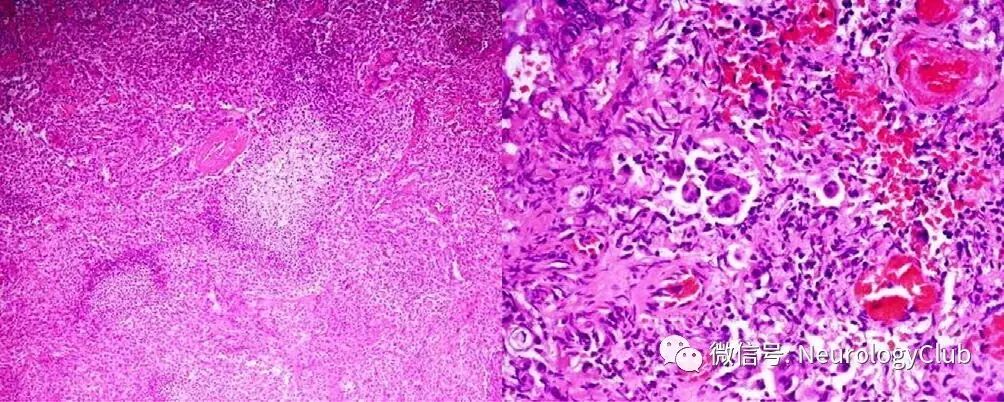

初诊医生考虑脑缺血,建议患者行MRI检查,提示右侧大脑凸面慢性硬膜下血肿,大小为12×12×20mm,伴有邻近脑组织水肿(图1)。

(图1:左:T2WI可见12×12×20mm右侧凸面高信号病灶伴中度占位效应;中:FLAIR可见右侧凸面高信号病灶伴其下脑组织水肿;右:T1WI可见稍高信号病灶)

脑膜瘤可占颅内肿瘤的25%,但扁平肥厚型脑膜瘤不常见,在所有脑膜瘤中仅2-9%。脑膜瘤的典型MRI特点为T1WI相较灰质呈等或稍低信号,T2WI相较灰质呈等或稍高信号。慢性硬膜下血肿在MRI的表现多变,由出血的时间(血肿分解产物组成)决定,在某些时期可能与脑膜瘤混淆。本例患者扁平肥厚型肿瘤形似慢性硬膜下血肿,在MRI上容易误诊,因其并非慢性硬膜下血肿的首选检查。

脑膜瘤误诊为慢性硬膜下血肿先前也有报道。单纯MRI平扫有时不足以区分两者。扁平肥厚型脑膜瘤的常见部位并非大脑凸面,且常伴有骨质增生(50-90%),但本例中均不明显。增强CT和MRI或有助于鉴别,可见均匀强化,骨质增生,钙化和血管受累。